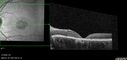

25 year old with Stargard and 2 ABCA4 mutations.vu 195 foisShe has worn glasses since she was a kid. Since she became an adult her vision started to deteriorate more rapidly. This seems to have been happening since she entered the accounting department for the last two years. Her vision is worse in the light especially when she is driving. She can see green lights in the night but not in the day. She sees better on a dark background than on a light background. Her mom is genetically visually impaired with Stargardts. Her father has RP. The mother was genetically tested in Boston about 23 years ago. That was when the gene was first being isolated. (The mother has seven brothers and sisters and four have stargardts and they are legally blind. Also one cousin has it.)

VA OD: Dcc20/160-1 PH20/80 Ncc20/200-2

VA OS: Dcc20/160-2 PH20/80-1 Ncc20/200-1

IOP: TP: OD:20 OS:21